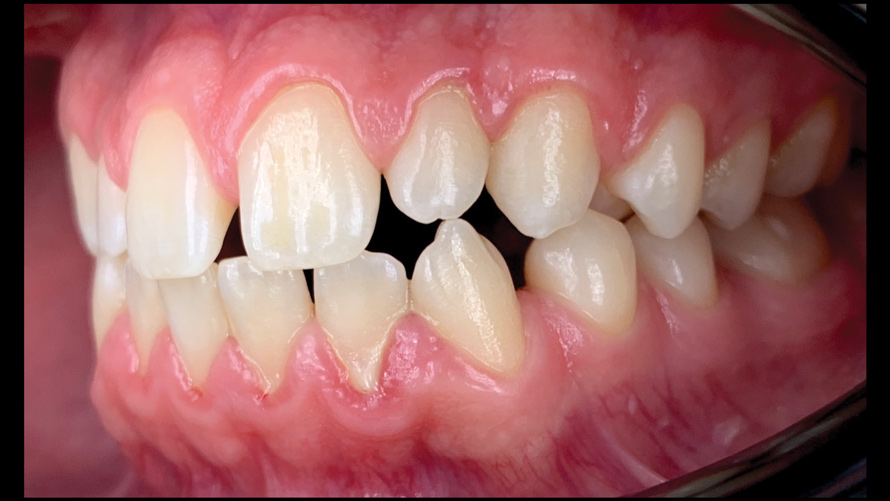

(12.) Intraoral photographs taken with a smartphone and an EALS device for orthodontic evaluation.

Figure 12

(13.) Intraoral photographs taken with a smartphone and an EALS device for orthodontic evaluation.

Figure 13